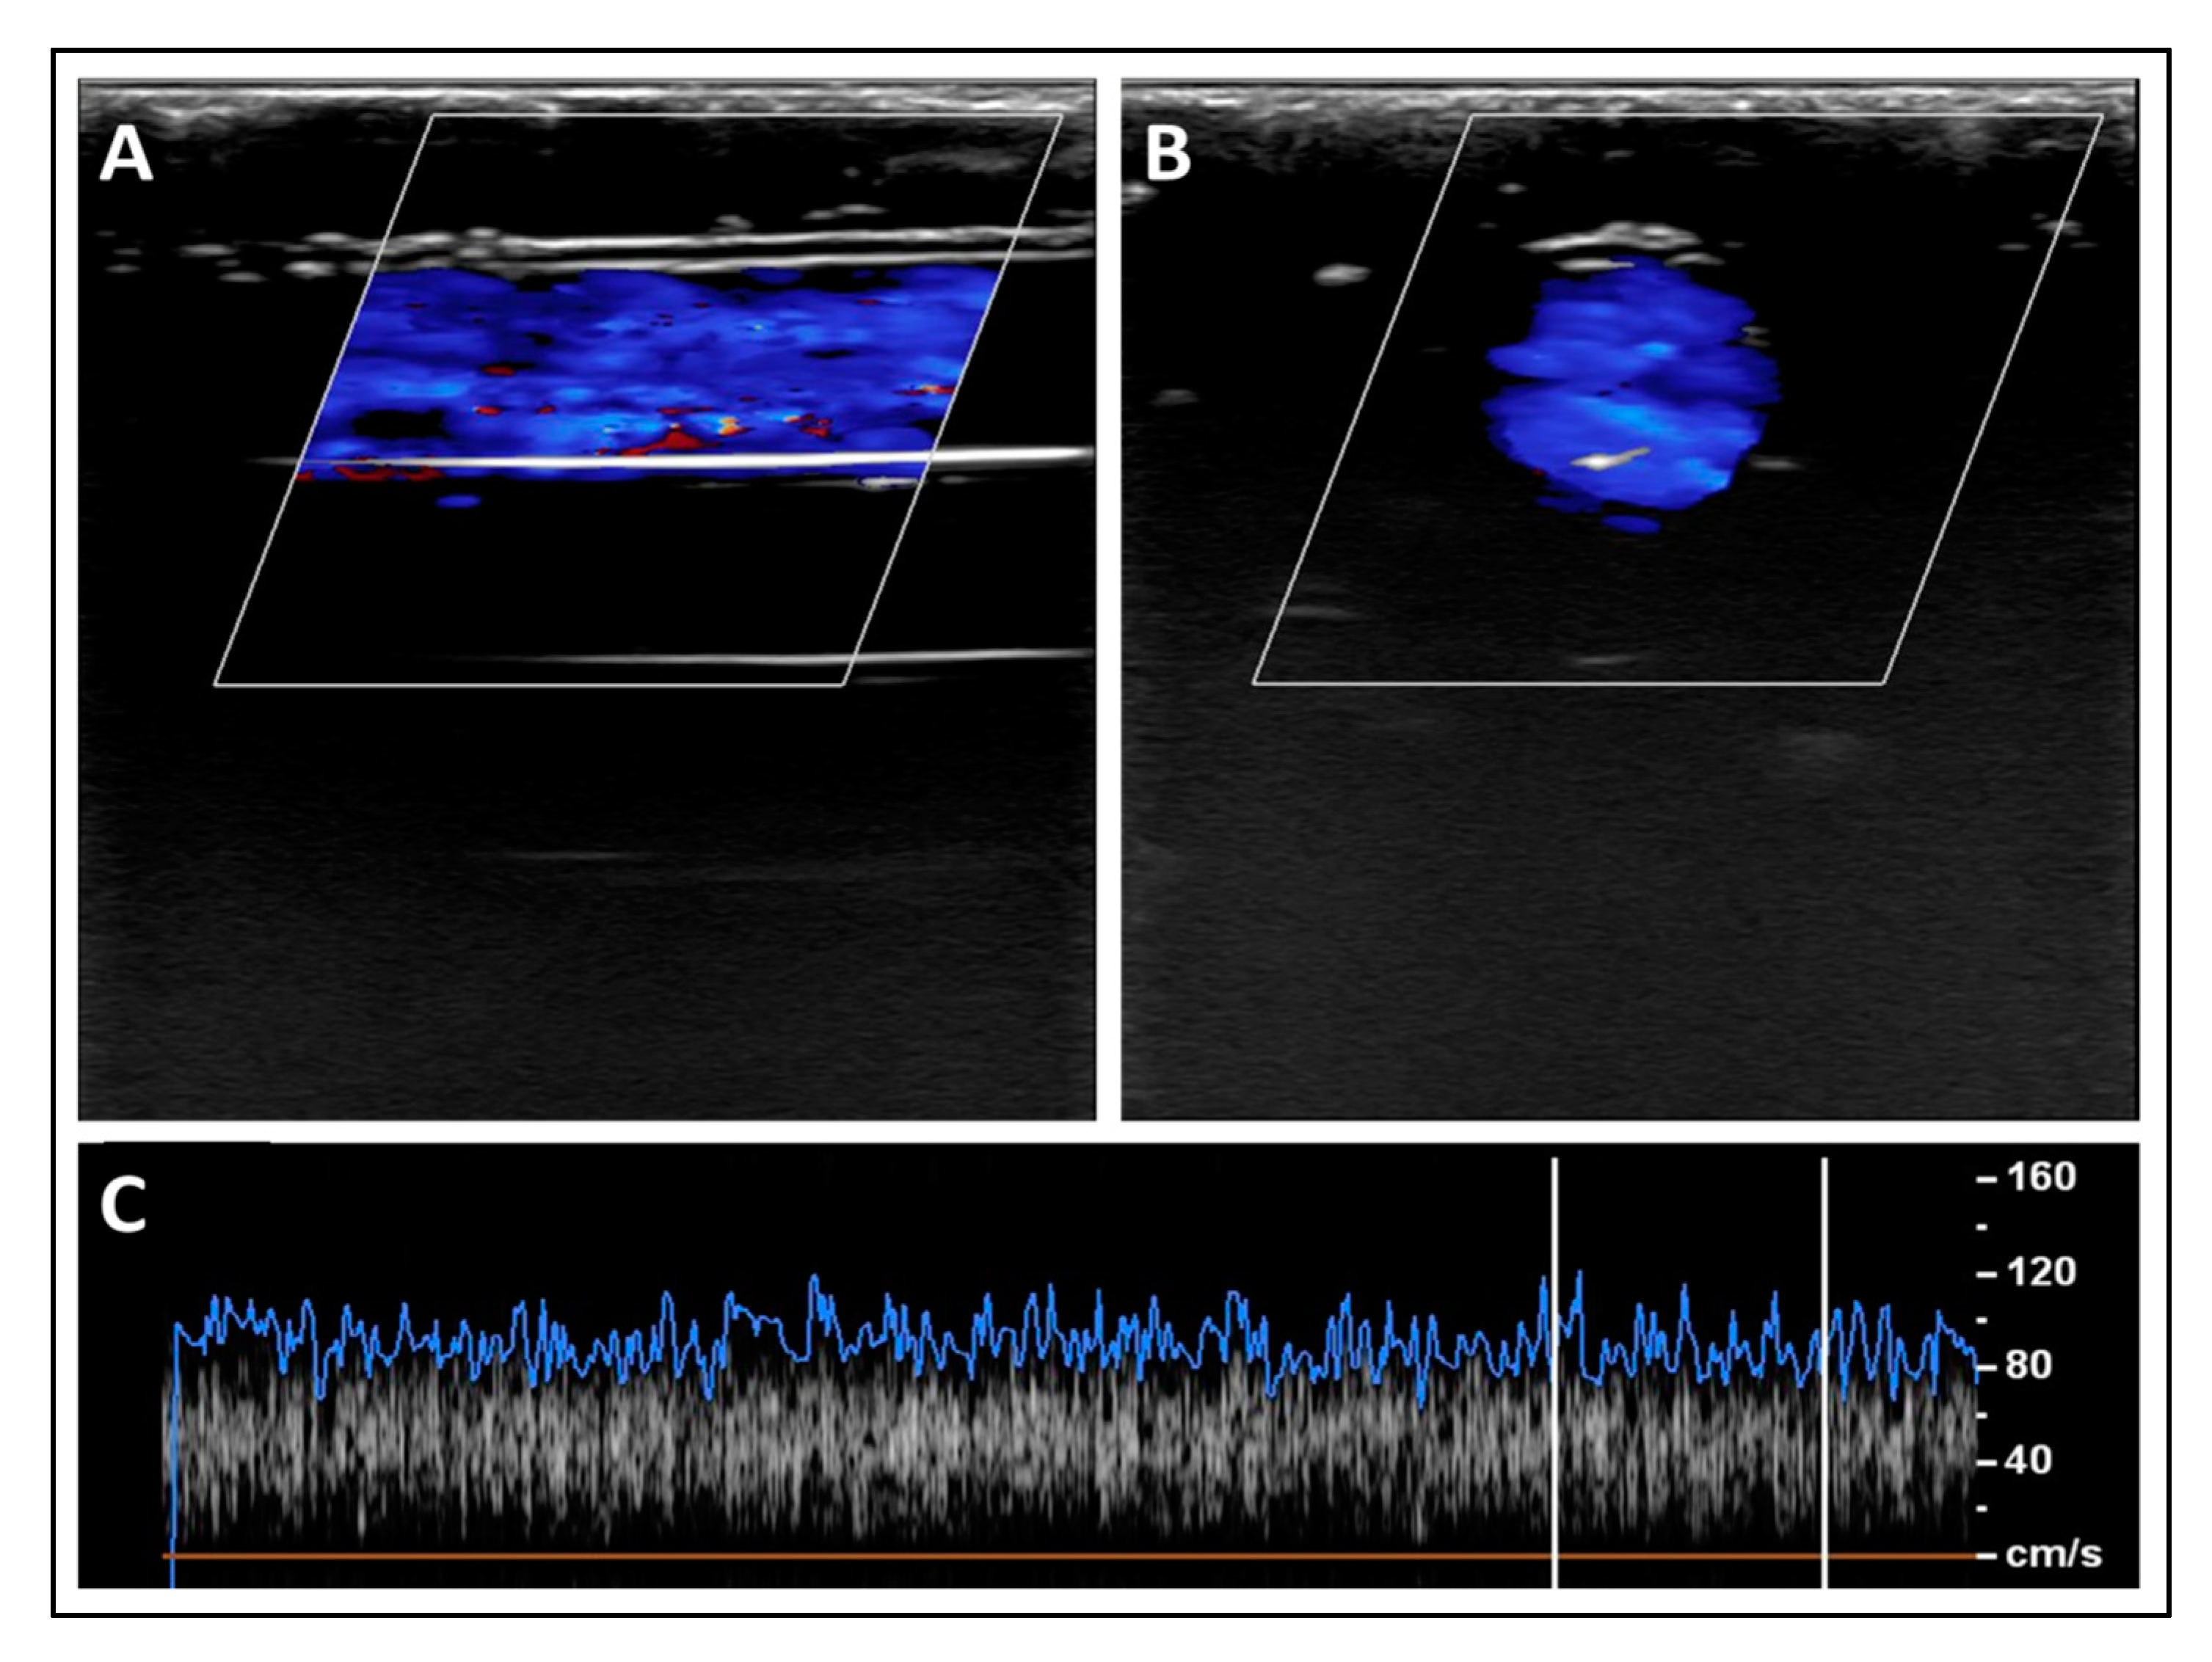

3.2. Experimental Validation of the Proposed Nanotechnology-Based Drug-Delivery System